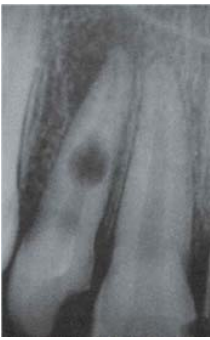

70.下圖中有何種牙齒相關的病變?

(A)Peg lateral (B)Supernumerary tooth (C)Odontoma (D)Taurodontism